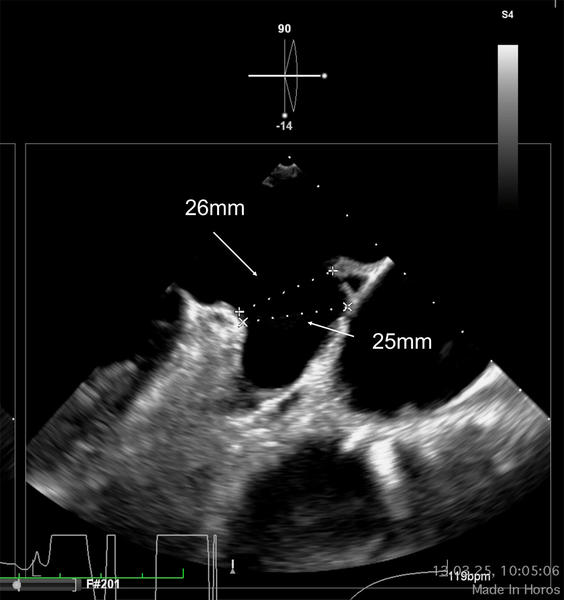

LAA closure - TOE sizing 0°/90°

LAA closure - sizing 0°/90°

Given the elevated thromboembolic risk with paroxysmal atrial fibrillation and GI bleeding under DOAC, the decision was made to plan a left atrial appendage occlusion followed by dual antiplatelet therapy for 3 months. A CT and a TOE was performed in this case for planning the procedure, as CT revealed a challenging morphology for both single- and double-disc devices with a shallow LAA (15mm depth) and an inferior-bend chicken wing morphology.

We have a chicken wing left atrial appendage morphology, with a landing zone maximum diameter within the 25-26 mm range, according to imaging tests. In these anatomies, I use to carefully assess the ostium diameters, which are not provided in this case, and I choose a disc approximately 10 mm larger in diameter than the ostium to ensure a complete seal, if the surrounding structures allow it. If using the Amulet device, the most appropriate implantation in this case would be obtained by a semi-sandwich technique, with a 31 mm device and a 38 mm disc. Again, this last aspect is crucial in this scenario to ensure a proper seal.